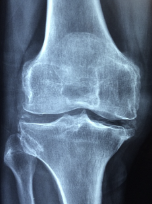

무릎 관절염은 단순 방사선 촬영 검사로 진단할 수 있으며, 관절 간격의 좁아짐과 골극 형성 등을 기준으로 초기/중기/말기 단계로 구분할 수 있습니다.